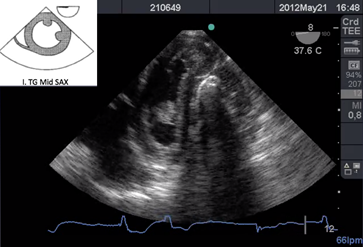

La salida de circulación extracorpórea (CEC) dificultosa es un evento que necesita ser reconocido para instaurar un tratamiento precoz. (Figura a)

Reconocer un ritmo de fibrilación ventricular y actuar desfibrilando de inmediato es el principal objetivo (Figura b), pero a continuación analizar la causa de la fibrilación, por ejemplo el ingreso de aire en la arteria coronaria derecha cuyo tratamiento es aumentar la presión de perfusión coronaria, reingresar a CEC y/o agregar s inotrópicos para aumentar la contractilidad; o una isquemia aguda de dicha arteria que lleva a la necesidad de realizar un puente venoso, tal es el caso de reconocer con ETE el signo de McConnel o signos de aumento de presión de cavidades derechas17. El aire puede ingresar también hacia la arteria pulmonar y observar esta situación a través de ETE nos obliga a informar al cirujano para lograr la completa desairación 18. (Figura cyFigura d)